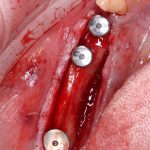

Я зафиксировал костный блок практически без адаптации на несколько винтов. Обрати внимание, что винты находятся в зоне, где не планируется установка имплантатов. Фиксация должна быть надежной, поскольку мне еще предстояла подготовка лунок для имплантатов. Трех винтов для этого вполне достаточно.

Напомню, что для этой работы я выбрал субкрестальные имплантаты Ankylos C/X. Они прекрасно сочетаются с любым методом остеопластики.

Я не планирую установку супраструктур или коронок, поэтому на уровень первичной стабильности можно положить болт. Даже наоборот — чем меньше крутящий момент при установке, тем лучше. Для имплантатов Ankylos и подобных им, это особенно важно. В общем, момент силы при установке — не более 10-15 Нсм.

Ремарка: имплантаты с предустановленными имплантодержателями хороши тем, что с ними легко контролировать позиционирование имплантатов. В случае с Ankylos С/Х - еще и крутящий момент. Имплантодержатель должен отсоединяться от имплантата с легким щелчком. Если его клинит, и тебе приходится прикладывать для этого усилия, то ты, однозначно, превысил момент силы во время установки имплантата. Следовательно, жди проблем.

Глянем на то, что получилось:

Осталось адаптировать костный блок (убрать острые края), проверить его фиксацию и, при необходимости, добавить винты. Десятисекундное дело.